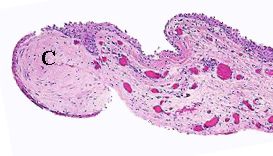

A specimen of pterygium containing corneal

stroma (C). The stroma of the conjunctiva shows

elastosis and presence of vasculature.

Pterygium with stromal elastosis.

(basophilic degeneration / staining)